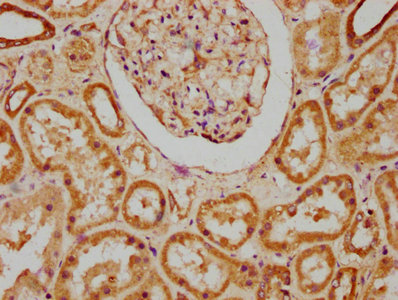

IHC image of CSB-PA878945LA01HU diluted at 1:200 and staining in paraffin-embedded human kidney tissue performed on a Leica BondTM system. After dewaxing and hydration, antigen retrieval was mediated by high pressure in a citrate buffer (pH 6.0). Section was blocked with 10% normal goat serum 30min at RT. Then primary antibody (1% BSA) was incubated at 4°C overnight. The primary is detected by a biotinylated secondary antibody and visualized using an HRP conjugated SP system.